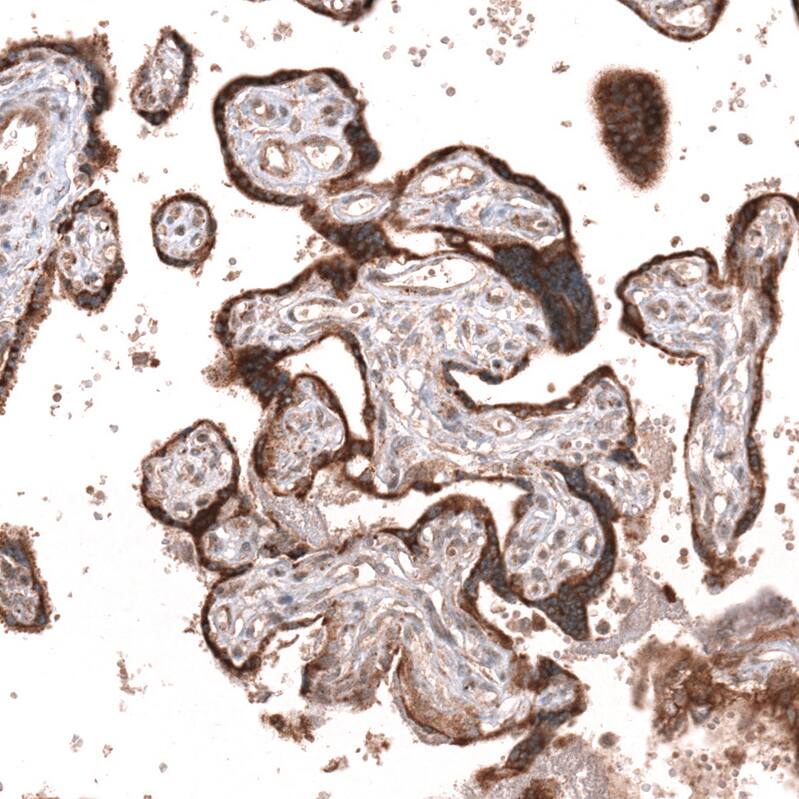

Staining of human placenta shows strong cytoplasmic positivity in trophoblastic cells.